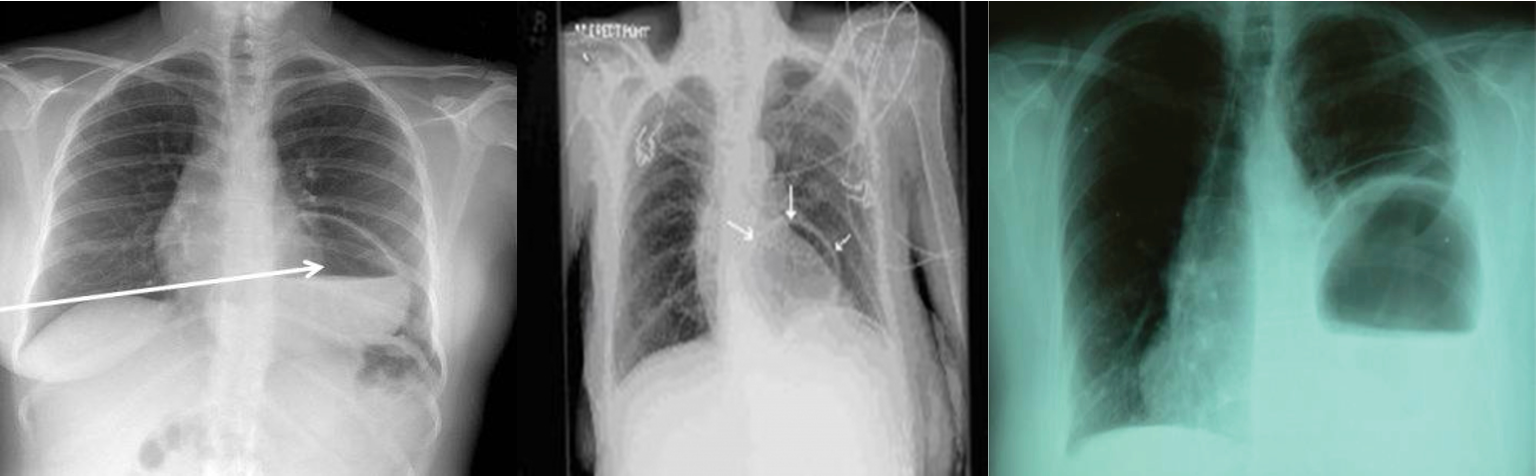

Hiatus Hernia